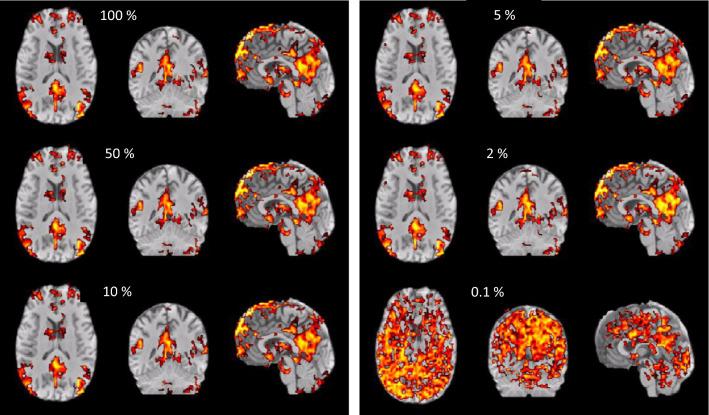

APPLICATIONS

Although the BOLD-response is rather slow, the high speed acquisition of MREG allows separation of BOLD-effects from cardiac and breathing related pulsatility. The increased sensitivity enables direct detection of the dynamic variability of resting state networks as well as localization of single interictal events in epilepsy patients. A separate and highly intriguing application is aimed at the investigation of the glymphatic system by assessment of the spatiotemporal patterns of cardiac and breathing related pulsatility.

尽管 BOLD 反应相当缓慢,但 MREG 的高速采集允许从心脏和呼吸相关脉动中分离出 BOLD 效应。灵敏度的提高使得能够直接检测静息状态网络的动态变化,并定位癫痫患者的单个癫痫发作事件。一个单独的、非常有趣的应用是通过评估心脏和呼吸相关脉动的时空模式来研究糖质系统。